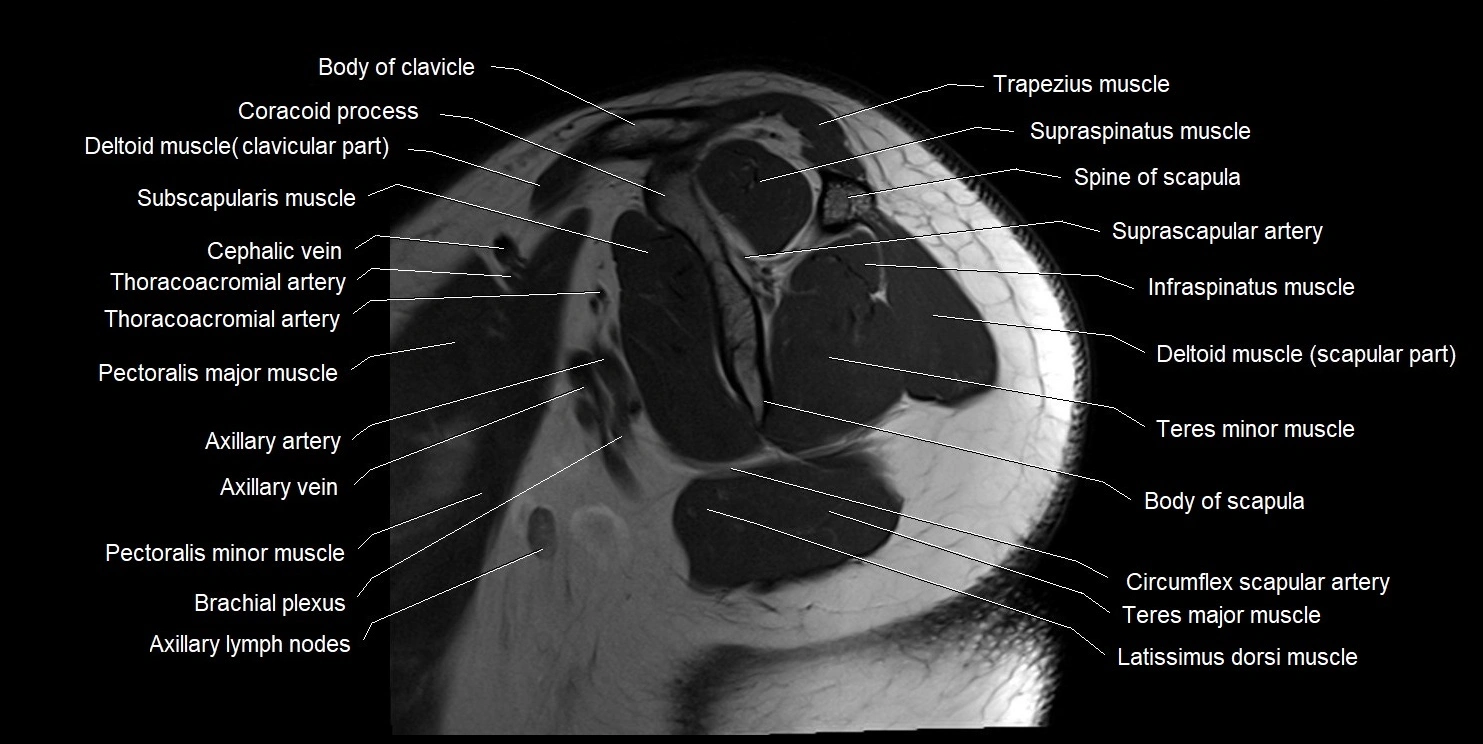

MRI images

image